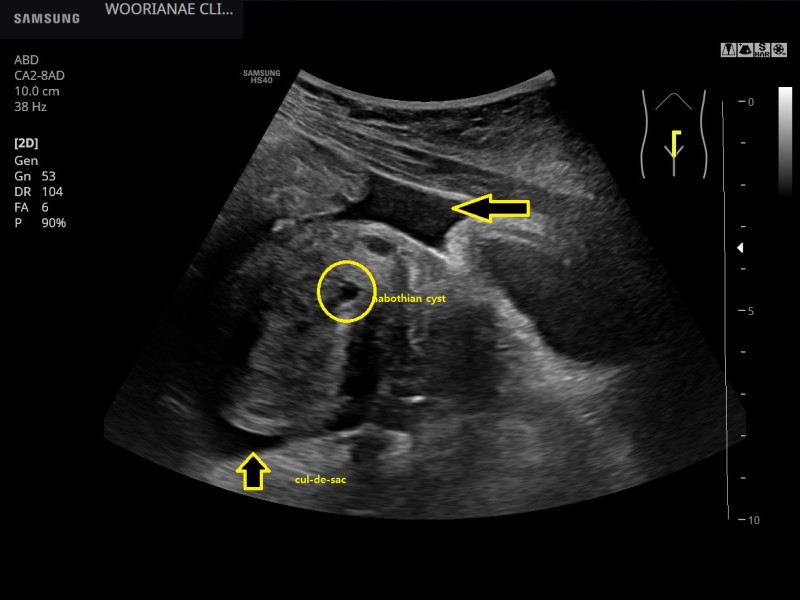

나보시안 낭종은 피부 세포가 자궁 경부의 점액 샘 출구를 막을 때 형성되는 작은 낭종 형태로 생기며 출산 및 자궁 경부에 대한 신체적 외상이 나보시안 낭종을 유발할 수 있습니다. 자궁 경부의 점액 샘은 정기적으로 점액을 생성하고 배출하는데 때로는 자궁 경부의 피부 세포가 이 점액 샘을 막으면서 분비샘에 점액을 가두면서 점액이 분비샘 내부에서 팽창하여 나보시안낭종을 만들기도 합니다.

자궁 경부 부위에 상처를 입으면 피부 세포는 해당 부위에서 상처를 치료하기 위해 세포분열이 증가합니다. 새로운 세포는 자궁경부의 조직에 가해진 손상을 복구하는 데 도움이 되기도 하지만 자궁 경부의 점액 샘을 차단하고 점액을 가두면서 나보시안낭종을 형성할 수 있습니다. 하지만 나보시안낭종은 통증, 불편함이나 다른 증상을 일으키지 않으므로 일상적인 검진을 하는 동안 발견되는 경우가 많습니다.

일반적으로 자궁경부는 월경 액이 자궁에서 질로 흐르고 정자가 질에서 자궁으로 들어갈 수 있도록 열려 있습니다. 그러나 임신 중에는 자궁경부가 닫히고 발달 중인 아기를 보호하게 되며, 아이가 태어난 후 점액선 위에 새로운 조직이 자라는, 화상이라고 하는 과정에서 피부 세포가 과도하게 생성되어 점액 샘을 차단하기도 합니다. 시간이 지남에 따라 점액 샘을 막으면서 나보시안낭종이 형성될 수 있습니다.

나보시안낭종은 점액의 양에 따라 이 낭종의 지름은 수 밀리미터에서 4㎝까지 다양합니다. 가까이서 보면 흰색 또는 노란색으로 보일 수 있습니다. 특히 큰 낭종이나 여러 개의 낭종이 생길 수 있으며, 드물기는 하지만 낭종이 너무 커져서 골반 검사 중에 의사가 자궁 경부에 접근하기 어려울 때도 있지만 대부분 증상이 거의 없으며 일상생활에 지장을 주지 않습니다.